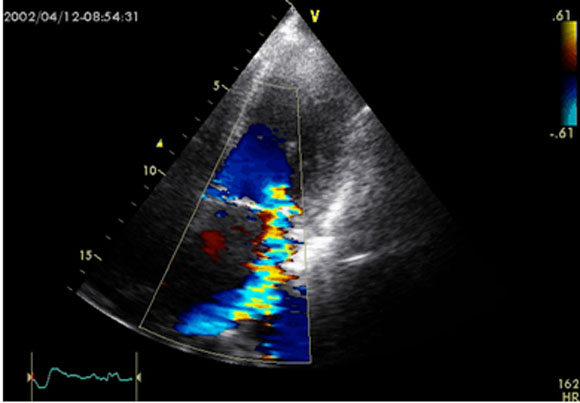

- 7 - Echocardiographie - Doppler